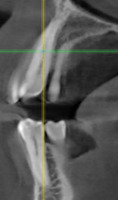

При анализе и описании компьютерной конусно-лучевой томографии (рис. 2а-г) была выявлена генерализованная первичная дегисценция вестибулярной пластинки кости от 1/2 до 3/4 длины корней зубов, зубной ряд целостный, все зубы витальны, кариозных поражений нет. Тип кости 1-2 (Lechkolm и Zarb, 1983), первичная дегисценция вестибулярной костной пластинки превышает пределы возрастной атрофии.

Через 12 месяцев (рис. 7а-г) на срезах компьютерной томограммы 11-ый и 13-ый зубы находятся в костной ткани, при этом костные пики и перегородки укрепились, объем их увеличился; вестибулярно заметен объем костной массы, предположительно компактной формации, исходя из электронной плотности участка. Этим объясняется отсутствие рецидива при лечении рецессии десны как в случае применения аутотрансплантата, также и ТМО (dura mater).